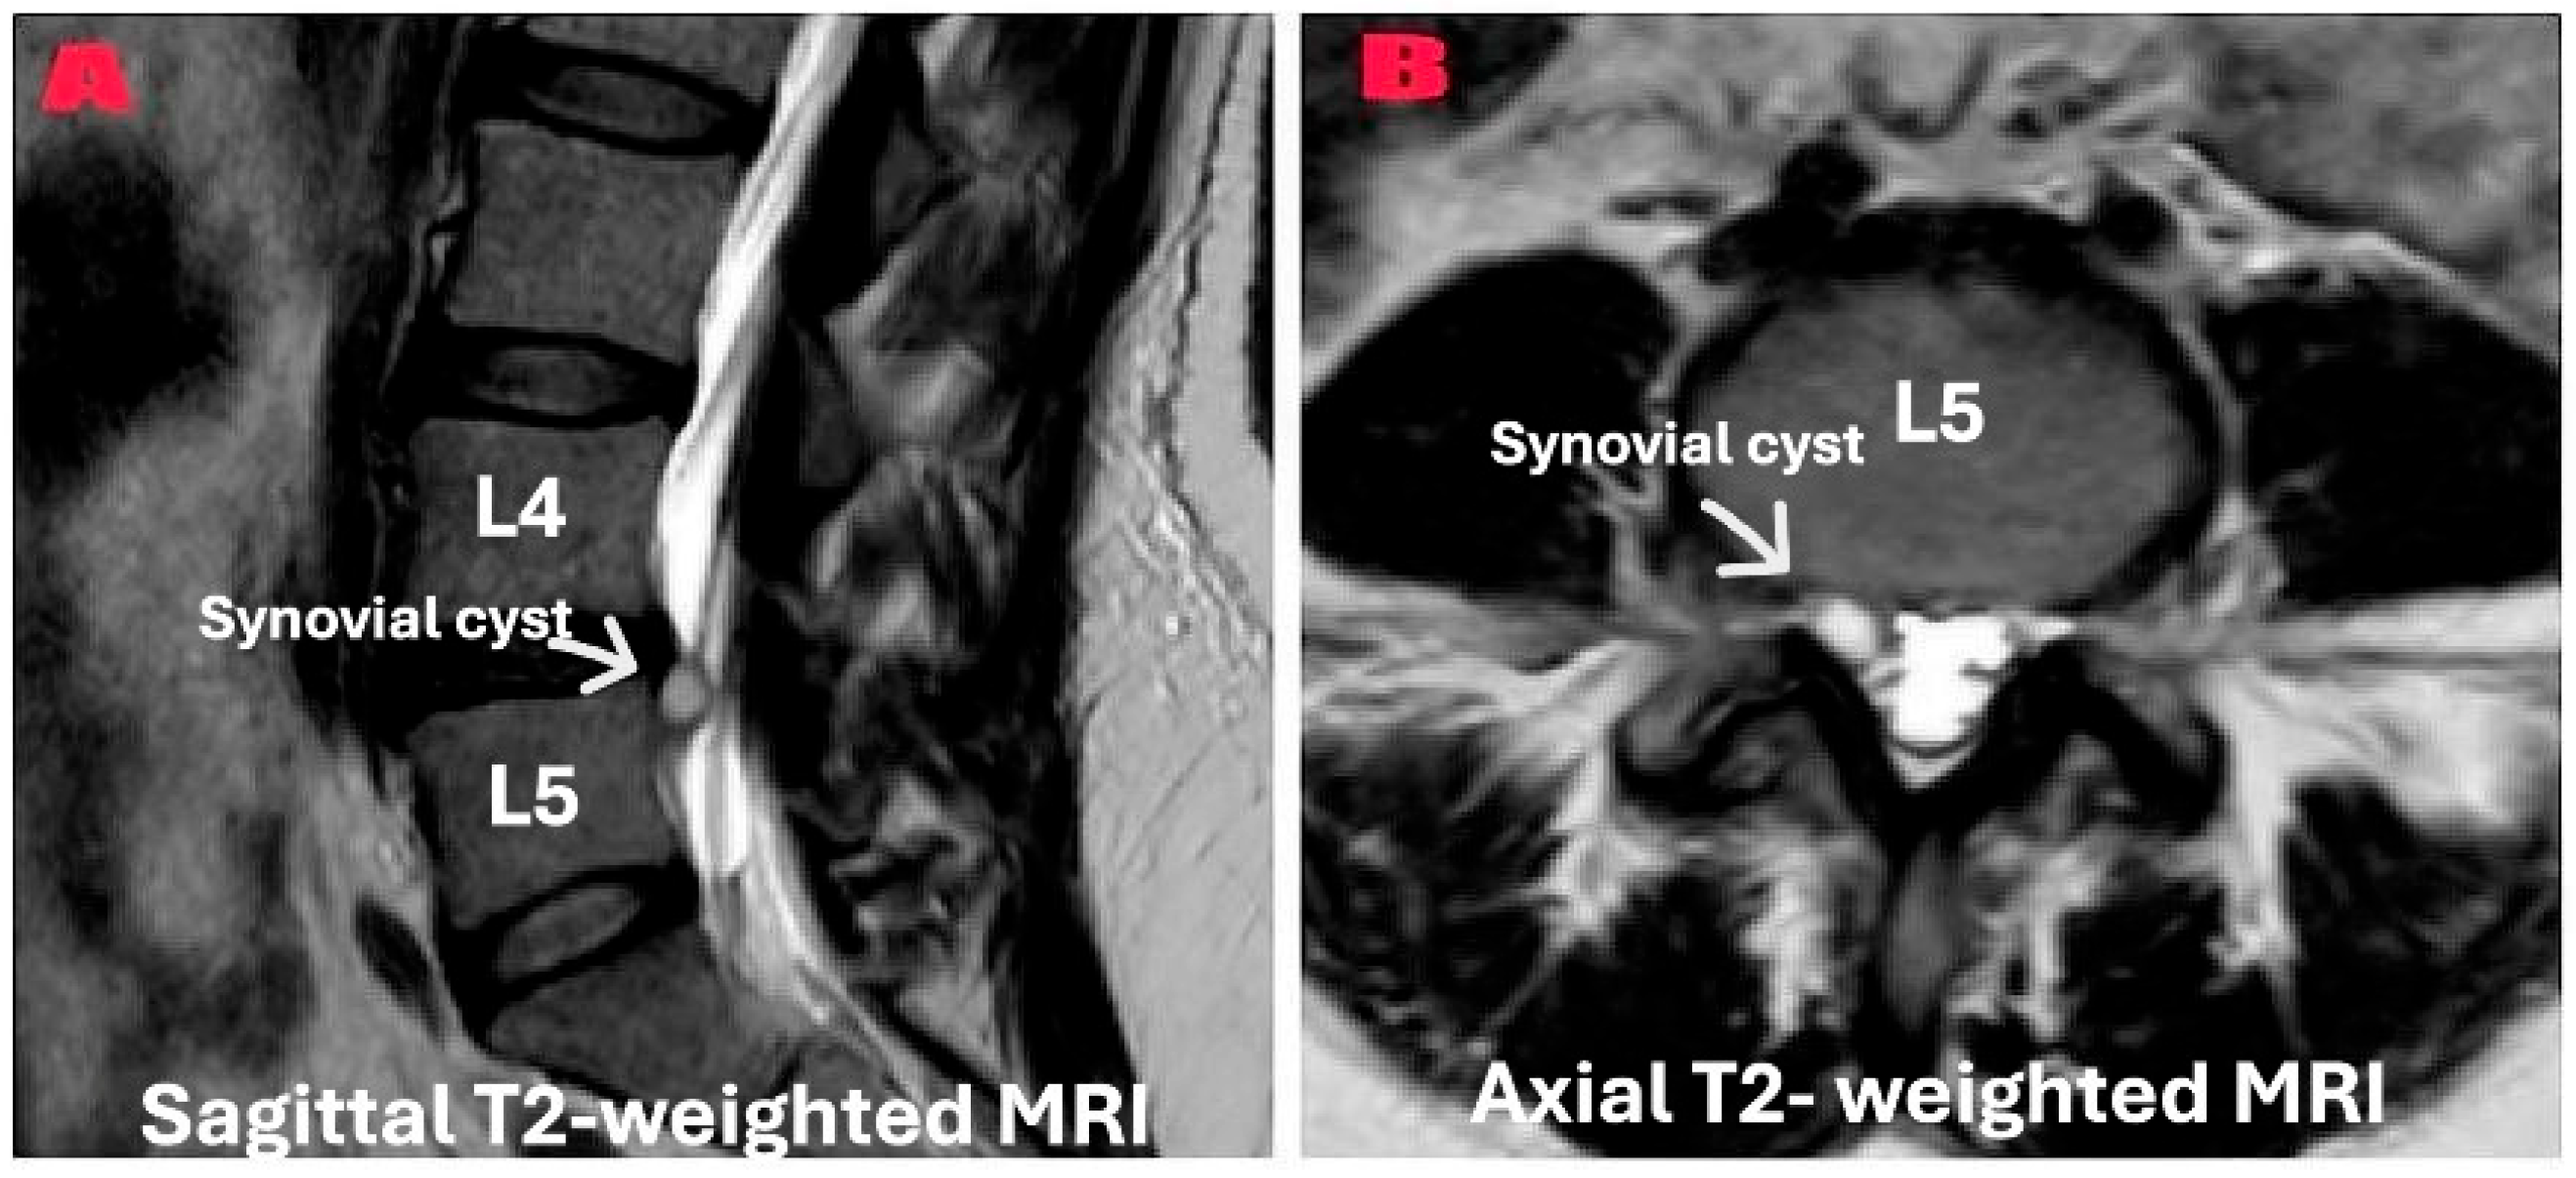

Preoperative MRI confirmed the diagnosis radiologically (Figure 1). Dynamic flexion-extension radiographs were obtained in all patients preoperatively (Figure 2) to evaluate segmental instability and to minimize selection bias that may occur due to the retrospective nature of the study. Cyst excision alone was performed in patients without instability according to imaging results, and unilateral dynamic instrumentation was performed (Figure 3) in addition to excision in patients with grade 1 instability according to the Meyerding classification. The systematic protocol used for decision-making reduced the impact of personal choices on selection of treatment. Patients with spondylolisthesis above grade 1 were not involved in the study. Exclusion of these patients provided sample homogeneity in addition to the biomechanic success of PEEK rod systems in mildly unstable cases due to their flexible designs.

Figure 1. Preoperative T2-weighted magnetic resonance imaging demonstrating lumbar synovial cyst at the L4–L5 level. (A) A sagittal T2-weighted image showing the synovial cyst (indicated by the white arrow) as a well-defined, fluid-intensity lesion in the posterior spinal canal between the L4 and L5 vertebrae, causing the compression of the dural sac. (B) An axial T2-weighted image of the same patient revealing the synovial cyst (indicated by the white arrow) in the right posterolateral aspect of the spinal canal, demonstrating a significant mass effect on the thecal sac and neural elements. The cyst exhibits high signal intensity in T2-weighted sequences because of its fluid content.